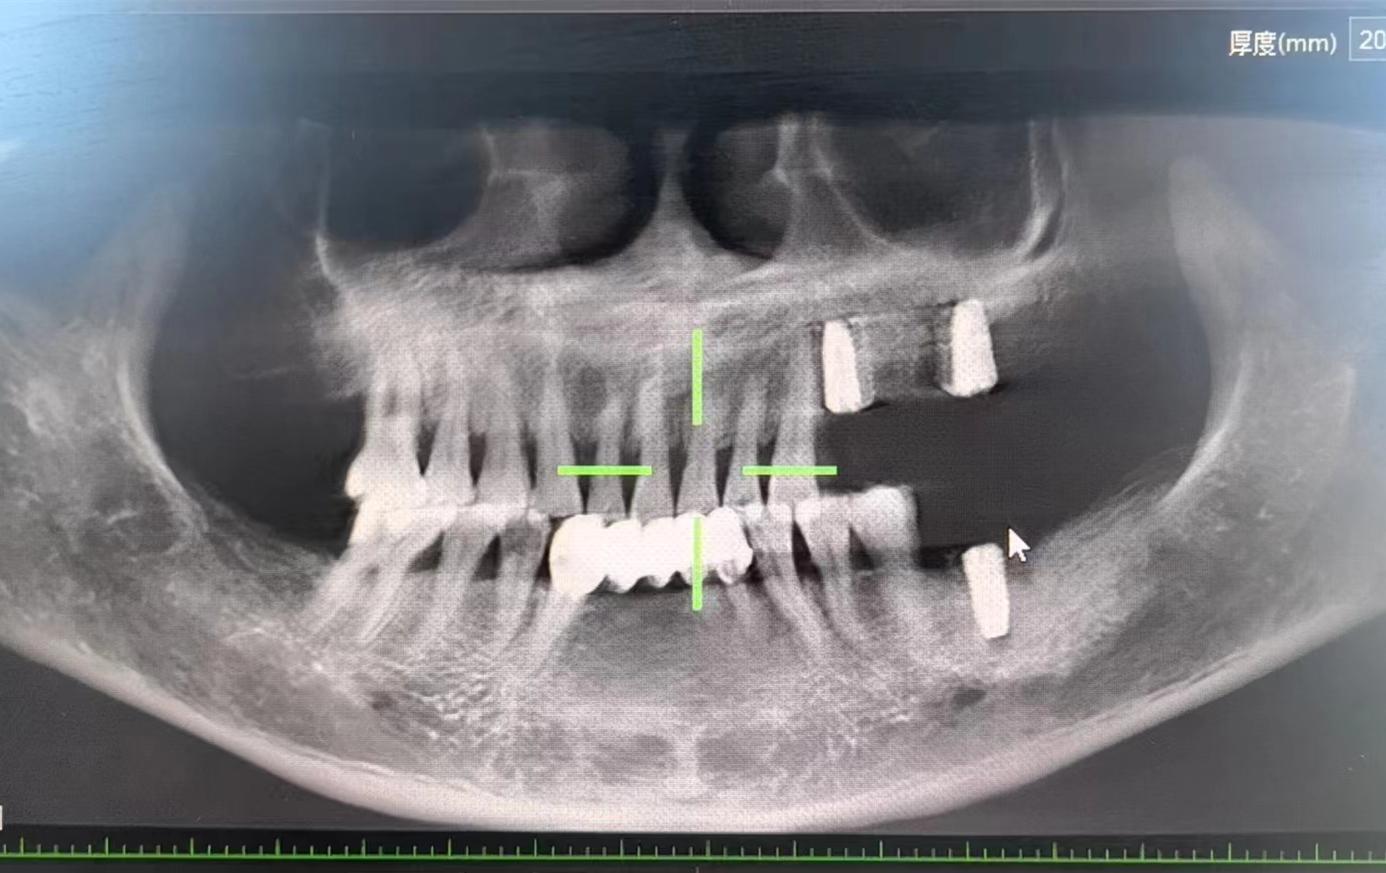

醫(yī)生檢查后,安排患者拍攝口腔CBCT,確定牙槽骨情況,并制定種植計(jì)劃,查血常規(guī),凝血功能,血壓,免疫檢查等。

為了避免患者在炎熱的夏季來(lái)回奔波,口腔科高艾玲主任團(tuán)隊(duì)決定為病人一次性種植三顆缺失的牙齒。辛璐醫(yī)生告訴患者,將通過(guò)牙科手術(shù)將人工牙根植入牙槽骨內(nèi),然后將牙齦縫合,大約10天左右拆線,之后等待骨愈合后進(jìn)行二期手術(shù)。

通過(guò)術(shù)中收集自體骨的形式,滿足了患者不能植人工骨的需求,以有利于患者的方式順利完成手術(shù)。